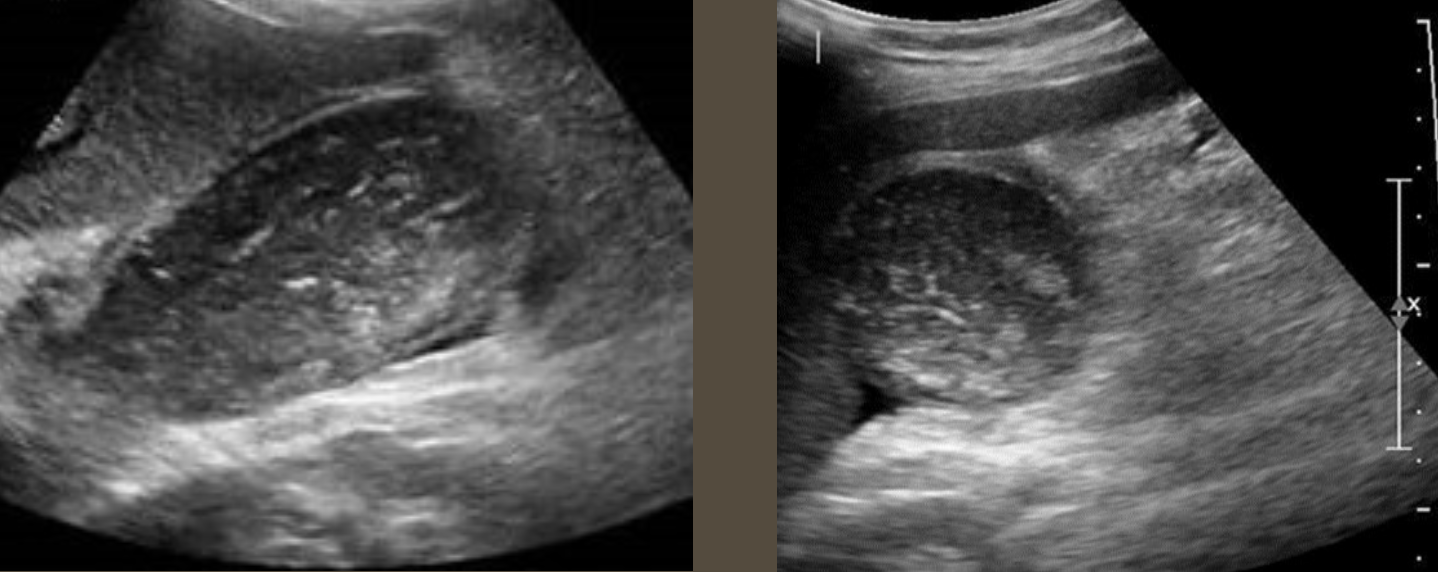

Splenic Trauma → blunt trauma usually resulting in hematoma

clinical hx: usually blunt abdominal trauma, underlying splenomegaly increased risk

s/sx: LUQ pain, low hematocrit from bleeding, abdominal swelling/bloating discomfort

2D US: capsule intact = subcapsular hematoma (conforms to spleen shape), ruptured capsule = free fluid/hematoma may form (check abdominal gutters for free fluid)

color doppler: avascular

DDX: splenic infarction, splenic abscess